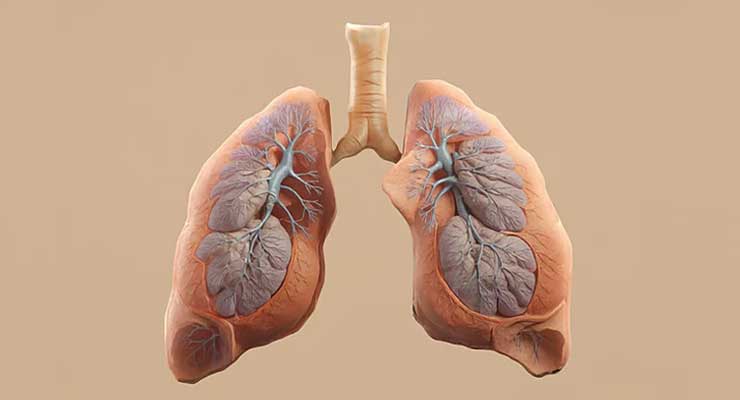

ই-সিগারেট বা ভেপকে অনেকেই প্রচলিত সিগারেটের তুলনায় কম ক্ষতিকর মনে করে থাকেন। তবে সাম্প্রতিক এক গবেষণায় উঠে এসেছে ভিন্ন চিত্র। নতুন এই গবেষণা বলছে, ই-সিগারেট ব্যবহারের ফলে ফুসফুস ও মুখগহ্বরের ক্যানসারের ঝুঁকি তৈরি হতে পারে। ফলে দেরি হওয়ার আগেই এ বিষয়ে সচেতন হওয়ার তাগিদ দিয়েছেন গবেষকেরা।

গবেষণার সঙ্গে যুক্ত এক সহলেখক জানান, ক্যানসার হওয়ার আগেই শরীরে কিছু সতর্ক সংকেত দেখা যায়। এর মধ্যে রয়েছে প্রদাহ বৃদ্ধি এবং ডিএনএ ক্ষতিগ্রস্ত হওয়া। গবেষণায় দেখা গেছে, ই-সিগারেট ব্যবহারের সঙ্গে এসব পরিবর্তনের সরাসরি সম্পর্ক রয়েছে। তার মতে, ভেপের ধোঁয়া মুখ, মুখগহ্বর এবং ফুসফুসের কোষে অস্বাভাবিক পরিবর্তন ঘটাতে সক্ষম।

যদিও ই-সিগারেট তুলনামূলক নতুন একটি উদ্ভাবন, যার ব্যবহার শুরু হয়েছে একবিংশ শতাব্দীর শুরুতে, তাই দীর্ঘমেয়াদে এর প্রভাব সম্পর্কে এখনই চূড়ান্ত সিদ্ধান্ত দেওয়া কঠিন। তবুও গবেষণায় যে শারীরিক পরিবর্তনের কথা বলা হয়েছে, তা ক্যানসারের পূর্বাভাস হিসেবে বিবেচিত হতে পারে।

গবেষণার নেতৃত্বদানকারী এক রোগতত্ত্ববিদ বলেন, প্রচলিত সিগারেট যে ফুসফুসের ক্যানসারের কারণ, তা প্রমাণ করতে প্রায় এক শতাব্দী সময় লেগেছিল। এ ক্ষেত্রে হাজার হাজার গবেষণা পরিচালনা করতে হয়েছে। যদিও সিগারেটের ক্ষতিকর দিক অনেক আগেই সন্দেহ করা হয়েছিল, তবুও তা দীর্ঘদিন উপেক্ষিত ছিল।